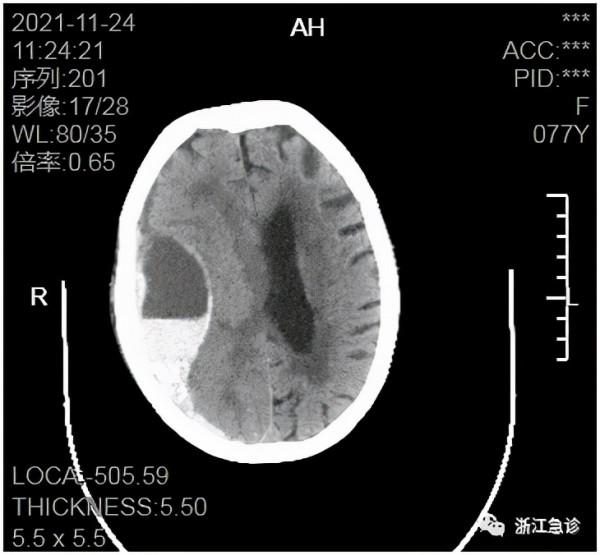

(入院後第五天頭顱CT)

仔細看CT的頭顱出血,已經不是一二天的事了。至此,突然出現心率減慢原因逐漸明晰起來了,很可能是顱內腦早期出血所致。顱內出血,腦內壓力就會增加,壓迫丘腦,可表現為心率減慢或伴有血壓升高。但心率慢,要想到是顱內問題或出血不是一件容易的事,何況這位患者的出血主要影響到顳葉,後者主要功能是支配抽象思維,輕度受壓後,抽象思維受到輕度影響,臨床上是很難注意到的(顱內出血如果影響到運動神經,就會出現肢體運動障礙,很容易發現)。